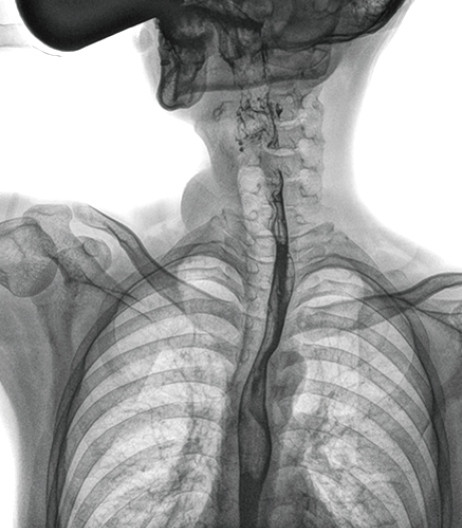

食管造影是食管病變的基本檢查方法,可以發(fā)現(xiàn)食管癌的特征性改變——食管粘膜的中斷和破壞,病人常感覺(jué)吞咽障礙,此特征在臨床中最常見(jiàn),也是早期食管癌的典型表現(xiàn)。一般伴隨的特征有管壁充盈缺損、龕影、軟組織塊影、食管腔狹窄等;在透視下還可看到食管壁僵硬、蠕動(dòng)緩慢等。

動(dòng)態(tài)DR能夠?qū)崿F(xiàn)大幅面透視,瞬時(shí)高清點(diǎn)片等。在食管造影檢查中,由于吞咽鋇劑后,造影劑流速非常快,在一個(gè)大幅面上方便觀察食管的病變。瞬時(shí)點(diǎn)片,可以實(shí)時(shí)捕捉到病變部位的影像,從而可以快速做出診斷。普利德多功能動(dòng)態(tài)DR擁有17×17英寸超大視野,一次曝光即可顯示整個(gè)食管,更方便觀察食管的病變,確定病變的范圍,對(duì)診斷和治療有重要參考價(jià)值。

與過(guò)去的數(shù)字胃腸機(jī)比較,動(dòng)態(tài)DR圖像分辨率高,對(duì)食管的全景觀察,局部粘膜破壞、中斷,管腔狹窄以及病灶范圍的顯示清晰度明顯更優(yōu)。

上消化道造影高清圖像

由此不難看出,動(dòng)態(tài)DR在食管造影的臨床應(yīng)用上,相比于其他檢查手段,成像清晰、應(yīng)用便捷,而且能夠充分顯示食管的局部和整體結(jié)構(gòu)形態(tài),并以此揭示相關(guān)形態(tài)和功能性改變,更有利于助力實(shí)現(xiàn)精準(zhǔn)診斷。